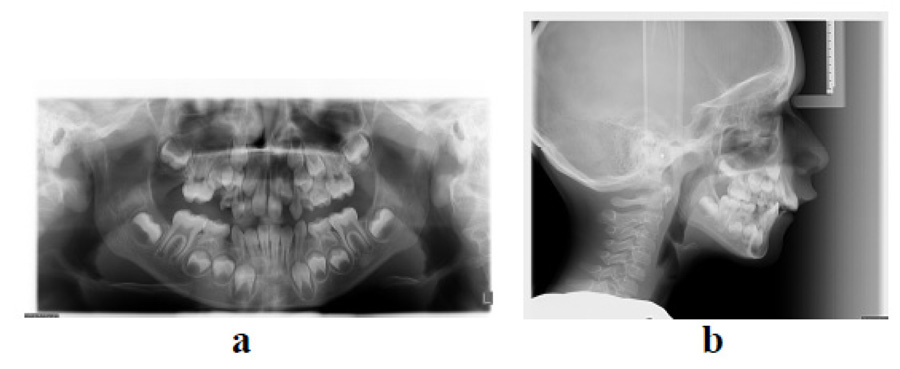

The patient had an asymmetric face with a convex facial profile. According to Schwarz typology [23], it was classified as an anteposition with retroinclinations (Fig. 1). Intraorally, the patient exhibited a Class II molar relationship, severely increased overjet (12 mm), and several carious deciduous teeth (Fig. 2). In addition to the general and dental history, photographs and impressions were taken, and panoramic and lateral x-rays were made (Fig. 3). Analysis of lateral cephalogram showed prognathic upper jaw and retrognathic lower jaw, skeletal Class II relationship, and borderline hyperdivergent (vertical) skeletal pattern (Fig. 3 and Table 1).

At the age of 12, new records were taken in order to plan the second phase of treatment. New photographs, intraoral scans, and x-rays were made (Fig. 5-7). After treatment, Class I molar relationship with normal overjet was obtained, the facial profile has improved. Panoramic x-ray indicated the presence of supernumerary root on the second right molar (Fig. 7). Analysis of lateral cephalogram showed improvement in parameters of sagittal relations, especially ANB, Wits appraisal, and SNA. There were no significant changes in vertical relations. Dental relations analysis noted proclination of both upper and lower incisors (Fig. 7 and Table 1).